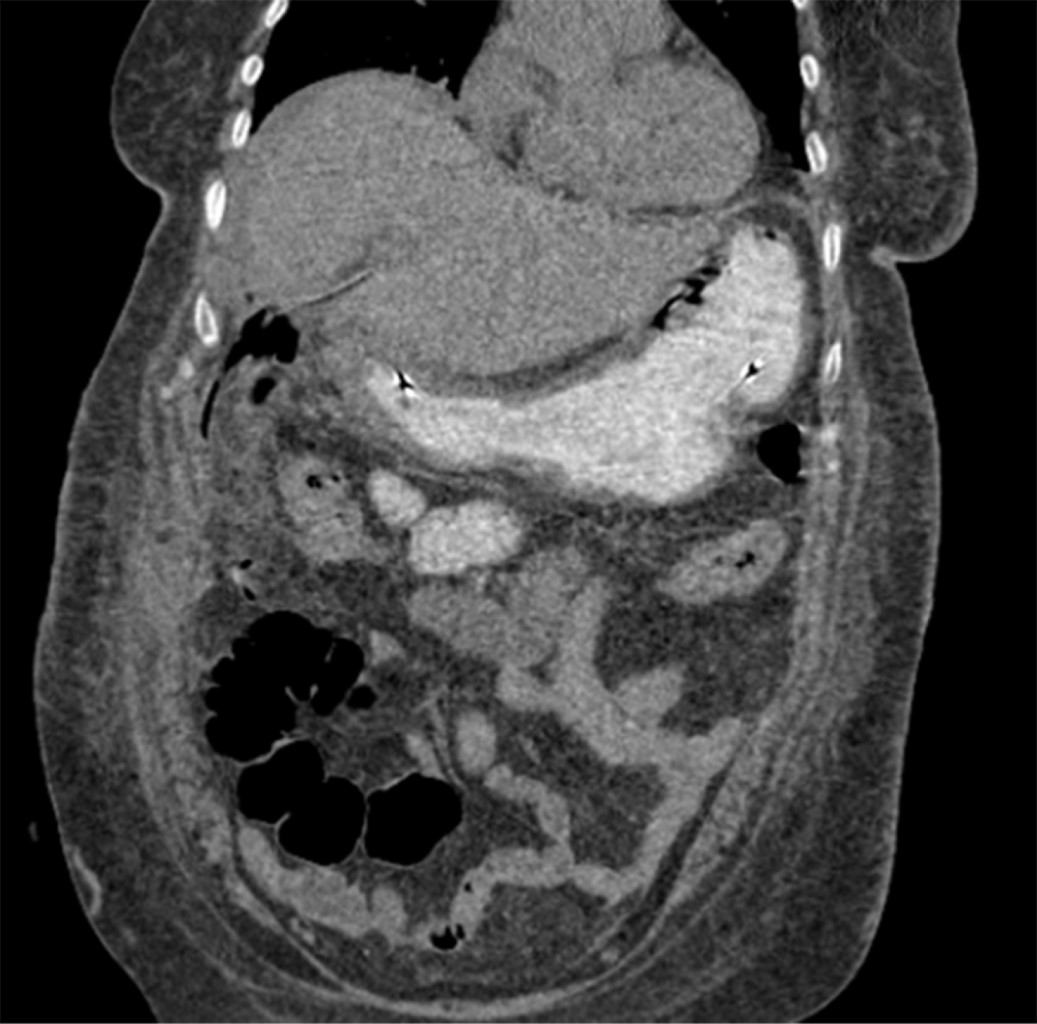

Por hallazgos a través de imagen se sospecha de fístula colecistogástrica, se programa para colecistectomía abierta. Observando como hallazgos, proceso adherencial importante, vesícula biliar escleroatrófica, se evidencia fístula colecistogástrica. Se procede a realizar gastrorrafia y extracción de lito de 2 × 3 cm, y cierre primario de la misma. Para mantener derivado el píloro, se optó por colocar una sonda nasoyeyunal. Se coloca sonda de colecistostomía (Figura 3).

En el postquirúrgico se inicia nutrición parenteral, posteriormente al quinto día postquirúrgico se realiza tomografía axial computarizada (TC) con contraste oral sin evidencia de fuga de medio de contraste (Figura 4), se decide iniciar vía oral, se egresa una semana después de la cirugía.

Figura 3

Figura 4